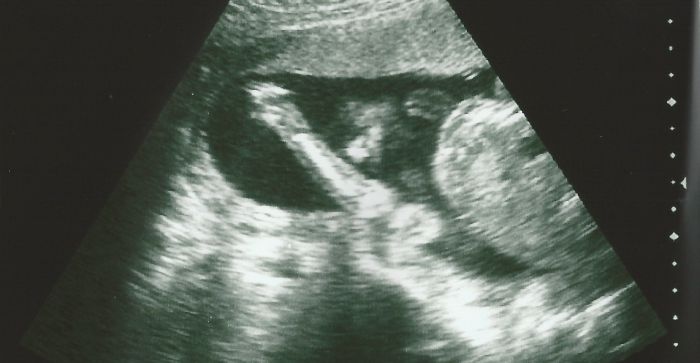

Laurinko, ty snímky jsou krásný, je na nich pěkně holčička vidět.

Jana: Jéé to je krásný snímeček, vážně krásné :)